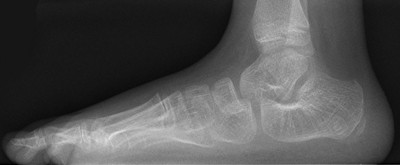

Radiologisch als een denkbeeldige as die door het midden van de talus wordt

getrokken, loodrecht op het gewrichtsvlak, niet uitkomt in het midden van het

eerste metatarsale bot van dig I. Normaal als de botten netjes in elkaars verlengde

staan hoort men een rechte lijn te kunnen trekken door metatarsale 1 en de tarsus.

platvoet |